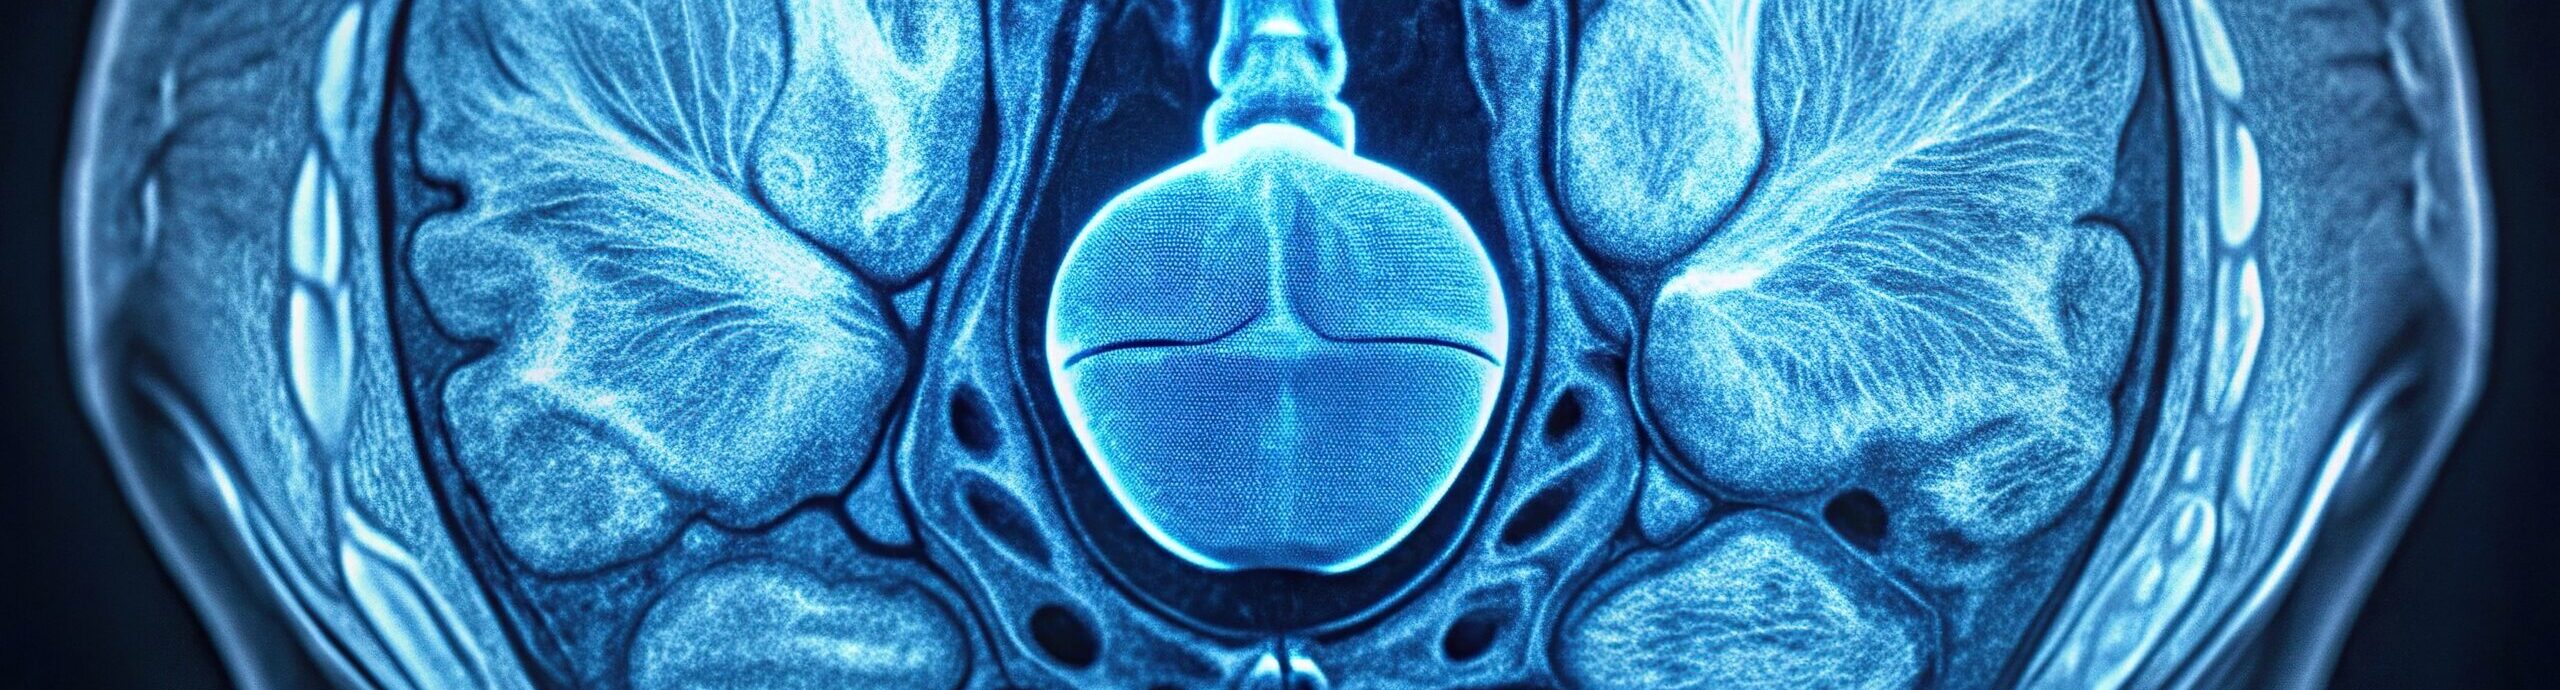

Diagnostics for prostate cancer

The basis of any effective therapy is a precise diagnosis.

The classic biopsy is still frequently used today as the standard method – although it only provides a reliable diagnosis in around 30-35% of cases. This is not good enough. Targeted therapy with few side effects requires much more precise information about the location, size and extent of a tumor – ideally before any tissue is removed.

At the VITUS Private Clinic, we use the latest diagnostic procedures to detect prostate cancer with the utmost accuracy – early, non-invasively and as gently as possible. Our methods clearly surpass conventional diagnostics in terms of informative value and reliability. This allows us to avoid unnecessary interventions, detect dangerous tumors in good time and offer tailor-made treatment strategies.

Prostate MRI